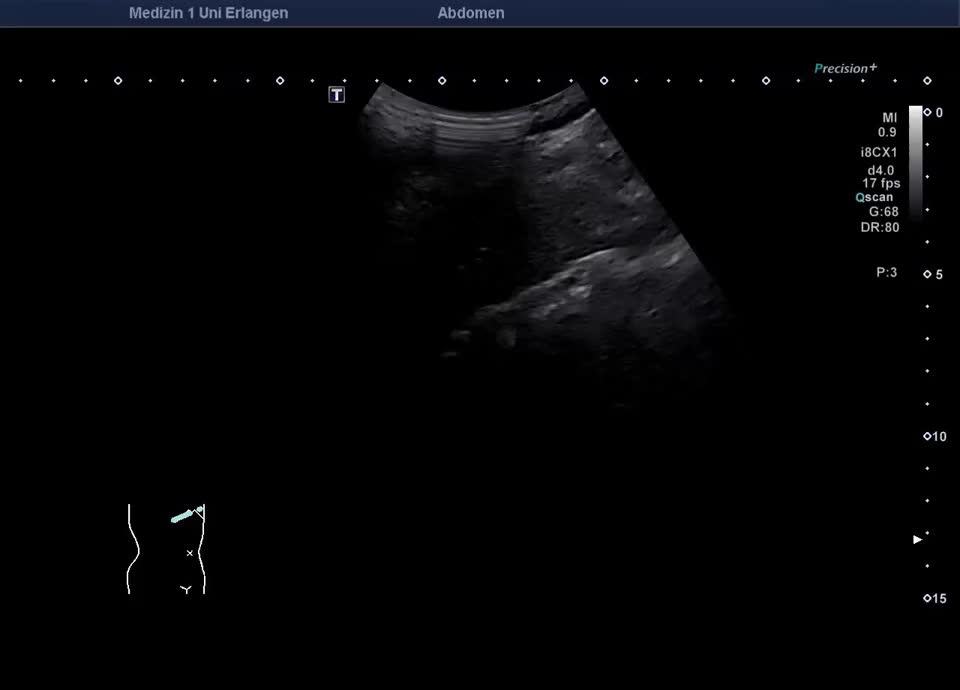

66-year-old male patient with a long-standing elevation of γ-GT since adolescence was referred for sonographic evaluation to exclude cholangiocellular carcinoma. B-mode ultrasound revealed an inhomogeneous liver parenchyma with diffusely distributed small comet-tail artifacts in the right liver lobe. The sonographic appearance was consistent with multiple biliary hamartomas (Von Meyenburg complexes). These consist of cysts, lined with biliary epithelium, and connective tissue, occur singly or in multiples, and typically measure 0.5–15 mm. Sonographically, they appear as echogenic nodules. To exclude malignancy-suspicious focal lesions, a contrast-enhanced ultrasound (CEUS) was performed. In correlation with the imaging findings and the known γ-GT elevation, there was no evidence of malignant liver disease. A single follow-up sonographic examination was scheduled.